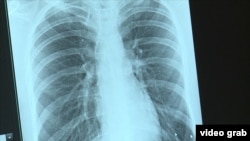

Если вовремя диагностировать туберкулез, то даже в лучшем случае человек на год или два будет прикован к больничной койке. Чтобы победить инфекцию в день такому пациенту могут давать до тридцати таблеток. Иначе - летальный исход. В мягком климате с туберкулезом можно прожить несколько лет, в суровом человек может погибнуть за несколько недель.

В целом по стране из ста тысяч россиян туберкулезом сегодня болеют 129 человек. Гораздо хуже статистика среди пациентов с диагнозом ВИЧ. Там счет заболевших идет уже на тысячи. Но врачи подчеркивают: это официальные данные, но не реальные показатели заболеваемости. Медики говорят, что могут только догадываться, сколько людей сегодня погибают от туберкулеза в России: ведь сотни из них умирают, так и не встав на врачебный учет или с другим официальным диагнозом.

"Когда мы делали анализ, выяснили: 45% обращавшихся в тубдиспансер флюорографию не делали несколько лет. И именно среди них выявляли случаи с большим распадом. То есть они нанесли вред не только своему здоровью, но и окружающим", – подчеркивает Константин Шалыгин.

Лучшее, что может сделать для профилактики туберкулеза любой россиянин прямо сейчас – записаться в свою поликлинику на флюорографию. Гражданам России по полису обязательного медицинского страхования эта услуга должна быть оказана бесплатно. Также важно понимать, что туберкулез – это больше не болезнь сословий, а инфекция, и она быстрее всего распространяется там, где пренебрегают элементарными санитарными требованиями. И третье, последнее: туберкулез ни в коем случае нельзя скрывать.